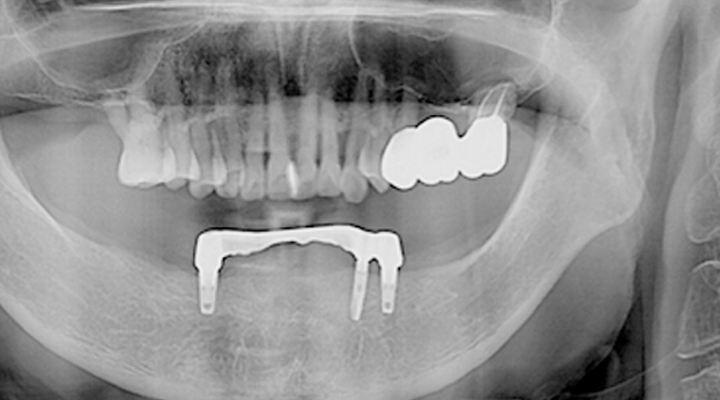

여러 개의 임플란트를 심은 뒤,

그 사이를 금속 막대로 연결해 튼튼한 지지대를 만들고,

그 위에 틀니를 안정적으로 고정하는 방식입니다.